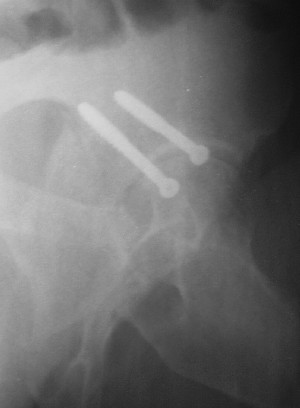

Привет! Вот недавно прооперировали похожий на ваш случай - впадина + шейка (правда у нас впадина поперечный+задний край). После травмы прошло 4 недели. мужчине 46 лет. С такой комбинацией все показания к первичному протезированию. Морально и технически мы к этому уже созрели.Но больной не собрал денег на протез. Выполнили остеосинтез впадины и шейки, прекрасно понимая, что головка вскоре рассосется, мы хотя бы надемся что к этому времени таз срастется, как говорится создали все условия для дальнейшего протезирования (может, и протез в последующем подешевле будет, в смысле, без укрепляющего кольца?). Привет Рункову!

Отправитель: Рунков 27 Сентябрь 2005, 09:57

Привет Алекей! Сделано неплохо, поздравляю, хотя второй винтик можно было бы и подлиннее в шейку загнать! Пара вопроов: доступ такой же? головка была свободной или висела на капсуле?

Отправитель: Алексей Смирнов 27 Сентябрь 2005, 22:35

Согласен, можно было и подлиннее. Доступ такой же - чрезвертельный, только разрез кожи прямой (а не Y, чего то я разницы не ощущаю). Головка была абсолютно свободной (то есть во время остеосинтеза таза лежала в стакане и не мешалась). Шансов, что она прирастет 0,00001%. Хотели даже выбросить, но привинтили как временный биологический протез (читай свободный трансплантат), чтоб на период срастания таза бедро проксимально не ушло (может ортопеды потом спасибо скажут). Ну а у вас первичное протезирование при переломе впадины тоже пока полько в планах?